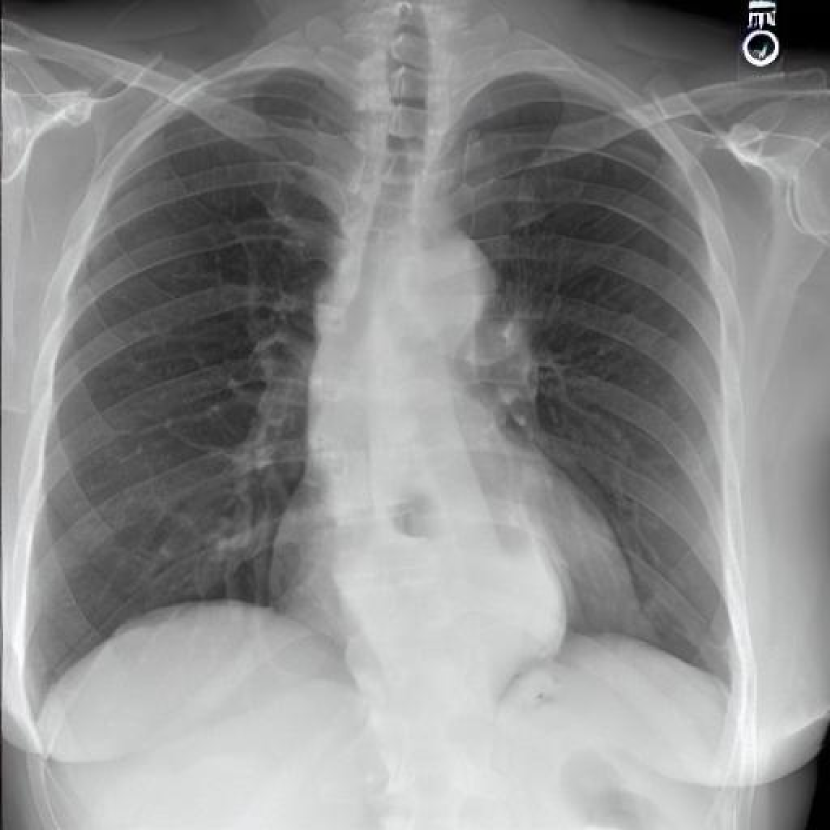

Leveraging Synthetic Data. With the advent of generative modelling tools, we are armed with the power to mitigate the problem of having a long-tail by supplementing the rare labels. We run a small experiment to evaluate whether we can use RoentGen [2], a prompt-based Stable Diffusion model to generate realistic chest X-rays and augment the training data. We generate about 5000 X-rays for training containing at least one pathology from the tail classes. We curate prompts for RoentGen by translating the Spanish reports available in the PadChest dataset to English, and also generate radiologist report-like prompts using ChatGPT 111chat.openai.com by providing curated templates. Figure 3 shows examples of prompts and the corresponding synthetic X-rays generated by RoentGen and verified by a radiologist.

Contribution of Synthetic Data. Figure 2 shows the increase in performance of the model over Table 1. This model was jointly finetuned on MIMIC CXR and a small synthetic dataset (refer Figure 3 for samples). Although the size of the synthetic dataset was too small for it to demonstrate an appreciable performance delta, these results show the promise of leveraging synthetic data to overcome the challenge of training on rare classes at least to some extent, especially since the biggest change is seen in the performance of the tail classes.